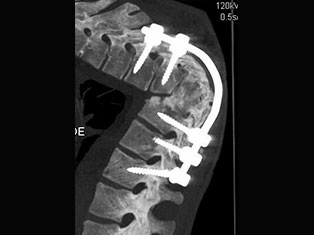

Degenerative Spine

The phrase "degenerative changes" in the spine refers to osteoarthritis of the spine. Osteoarthritis is the most common form of arthritis. Doctors may also refer to it as degenerative arthritis or degenerative joint disease.